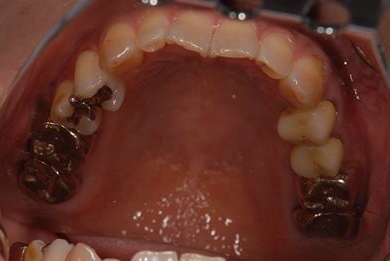

治療前

• 治療前